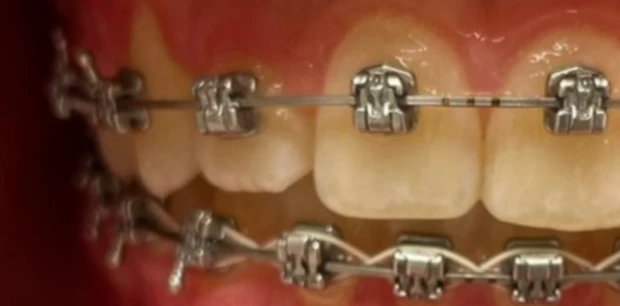

Ортодонтия

Исправление прикуса и выравнивание зубов брекет-системой

Пациент У., 15 лет. Родители обратились с жалобами на неровные зубы сына. Проведено ортодонтическое лечение брекет-системами. Лечение проводилось 2 года.